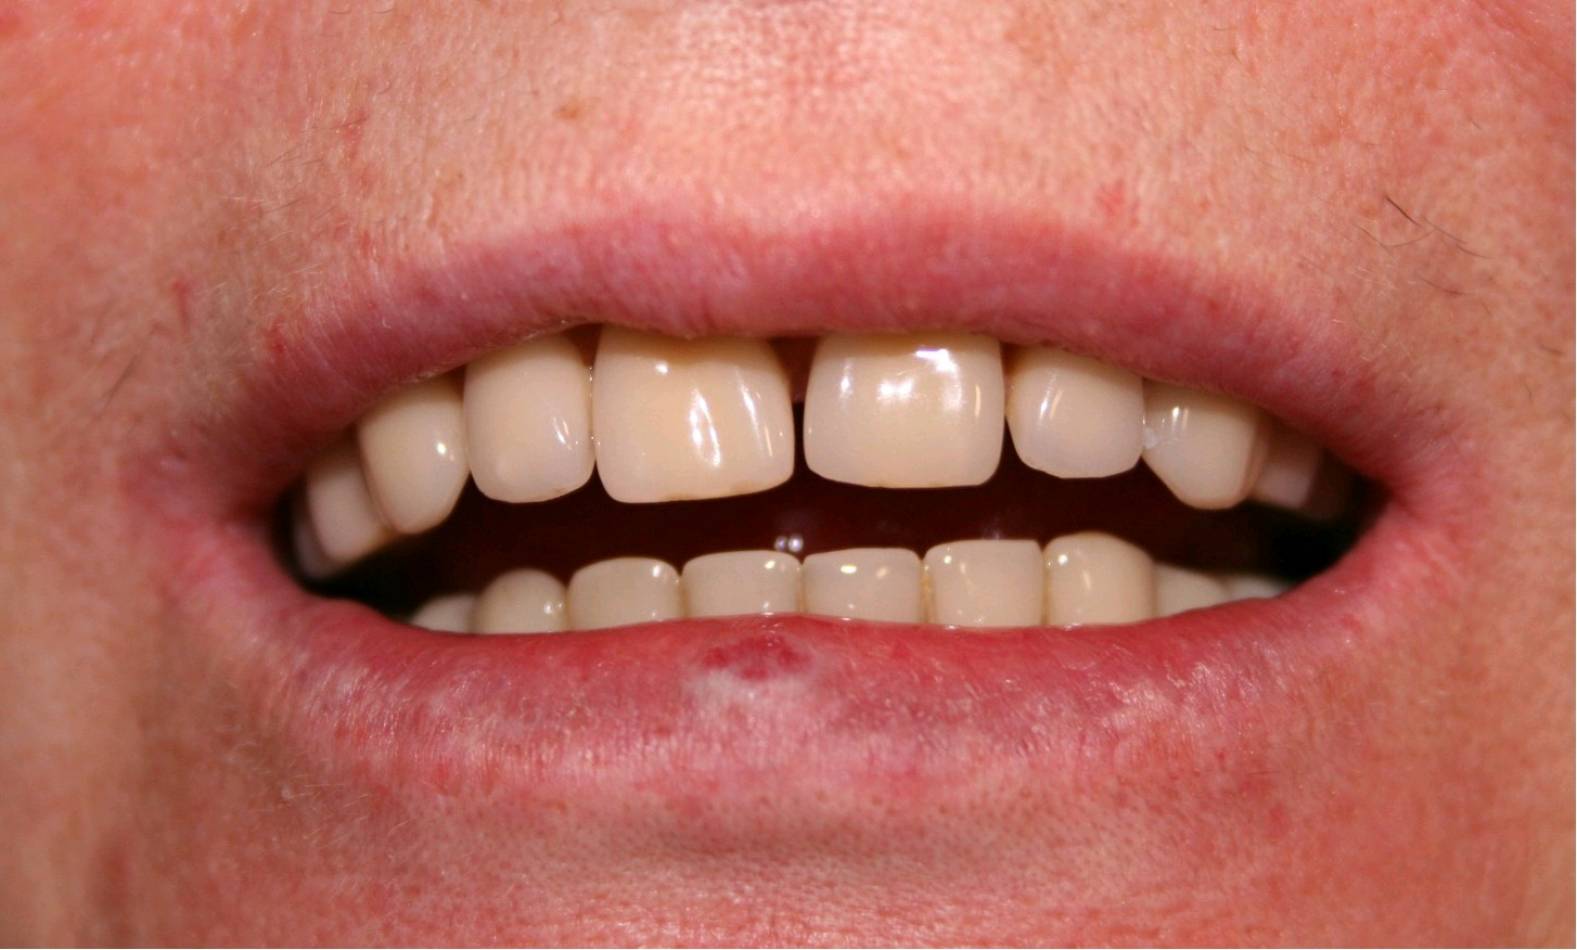

Implantologia e Chirurgia

Si effettua implantologia con impianti STRAUMANN e tecnologia IDI EVOLUTION.